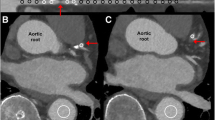

On adenosine stress CTP, eight patients (40 %) and 17 vascular territories (28 %) demonstrated perfusion abnormalities (example shown in Fig. 2). In patients with perfusion defects on CTP, two (10 %) had a defect involving one vessel territory, one (5 %) had defects involving two vessel territories and four (20 %) had defects involving three vessel territories. Of these, eight (13 %) were located in the LAD territory, four (7 %) in LCx territory and five (8 %) in the RCA territory. Nine (53 %) were transmural defects and eight (47 %) were non-transmural. All vascular territories with perfusion abnormalities identified on CTP were reversible using resting CTA for comparison, with six (35 %) partially reversible, and 11 (65 %) completely reversible.

Demonstration of obstructive coronary stenosis causing perfusion abnormality demonstrated by all techniques. A 66-year-old man with exertional chest pain. a CTA demonstrates mixed plaque resulting in >70 % stenosis in the mid left anterior descending (LAD) artery (white arrows). b Adenosine stress CTP shows perfusion defects in the mid-anteroseptal, apical septal and apical anterior myocardial segments (yellow arrows, upper panels) with normal perfusion on resting images (lower panels), indicating reversible LAD territory ischaemia. c Invasive angiography in the cranial left anterior oblique view demonstrates a long segment of severe stenosis in the mid LAD between proximal (P) and distal (D) reference points (77 % by QCA). d Short axis, horizontal and vertical long-axis SPECT-MPI images show a reversible perfusion defect in the mid anterior and apical segments